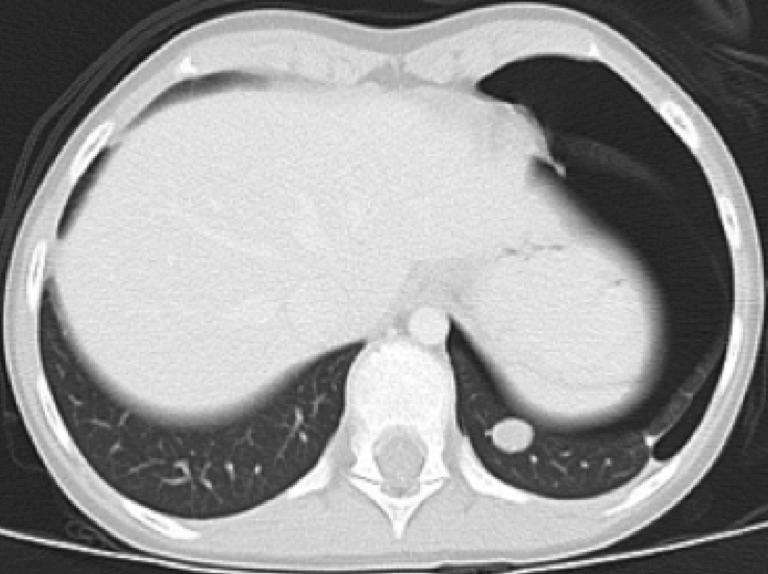

The most effective treatment to improve event free survival in this patient with metastatic Wilms tumor is

Your recommendation for management of this patient with metastatic Wilms tumor is